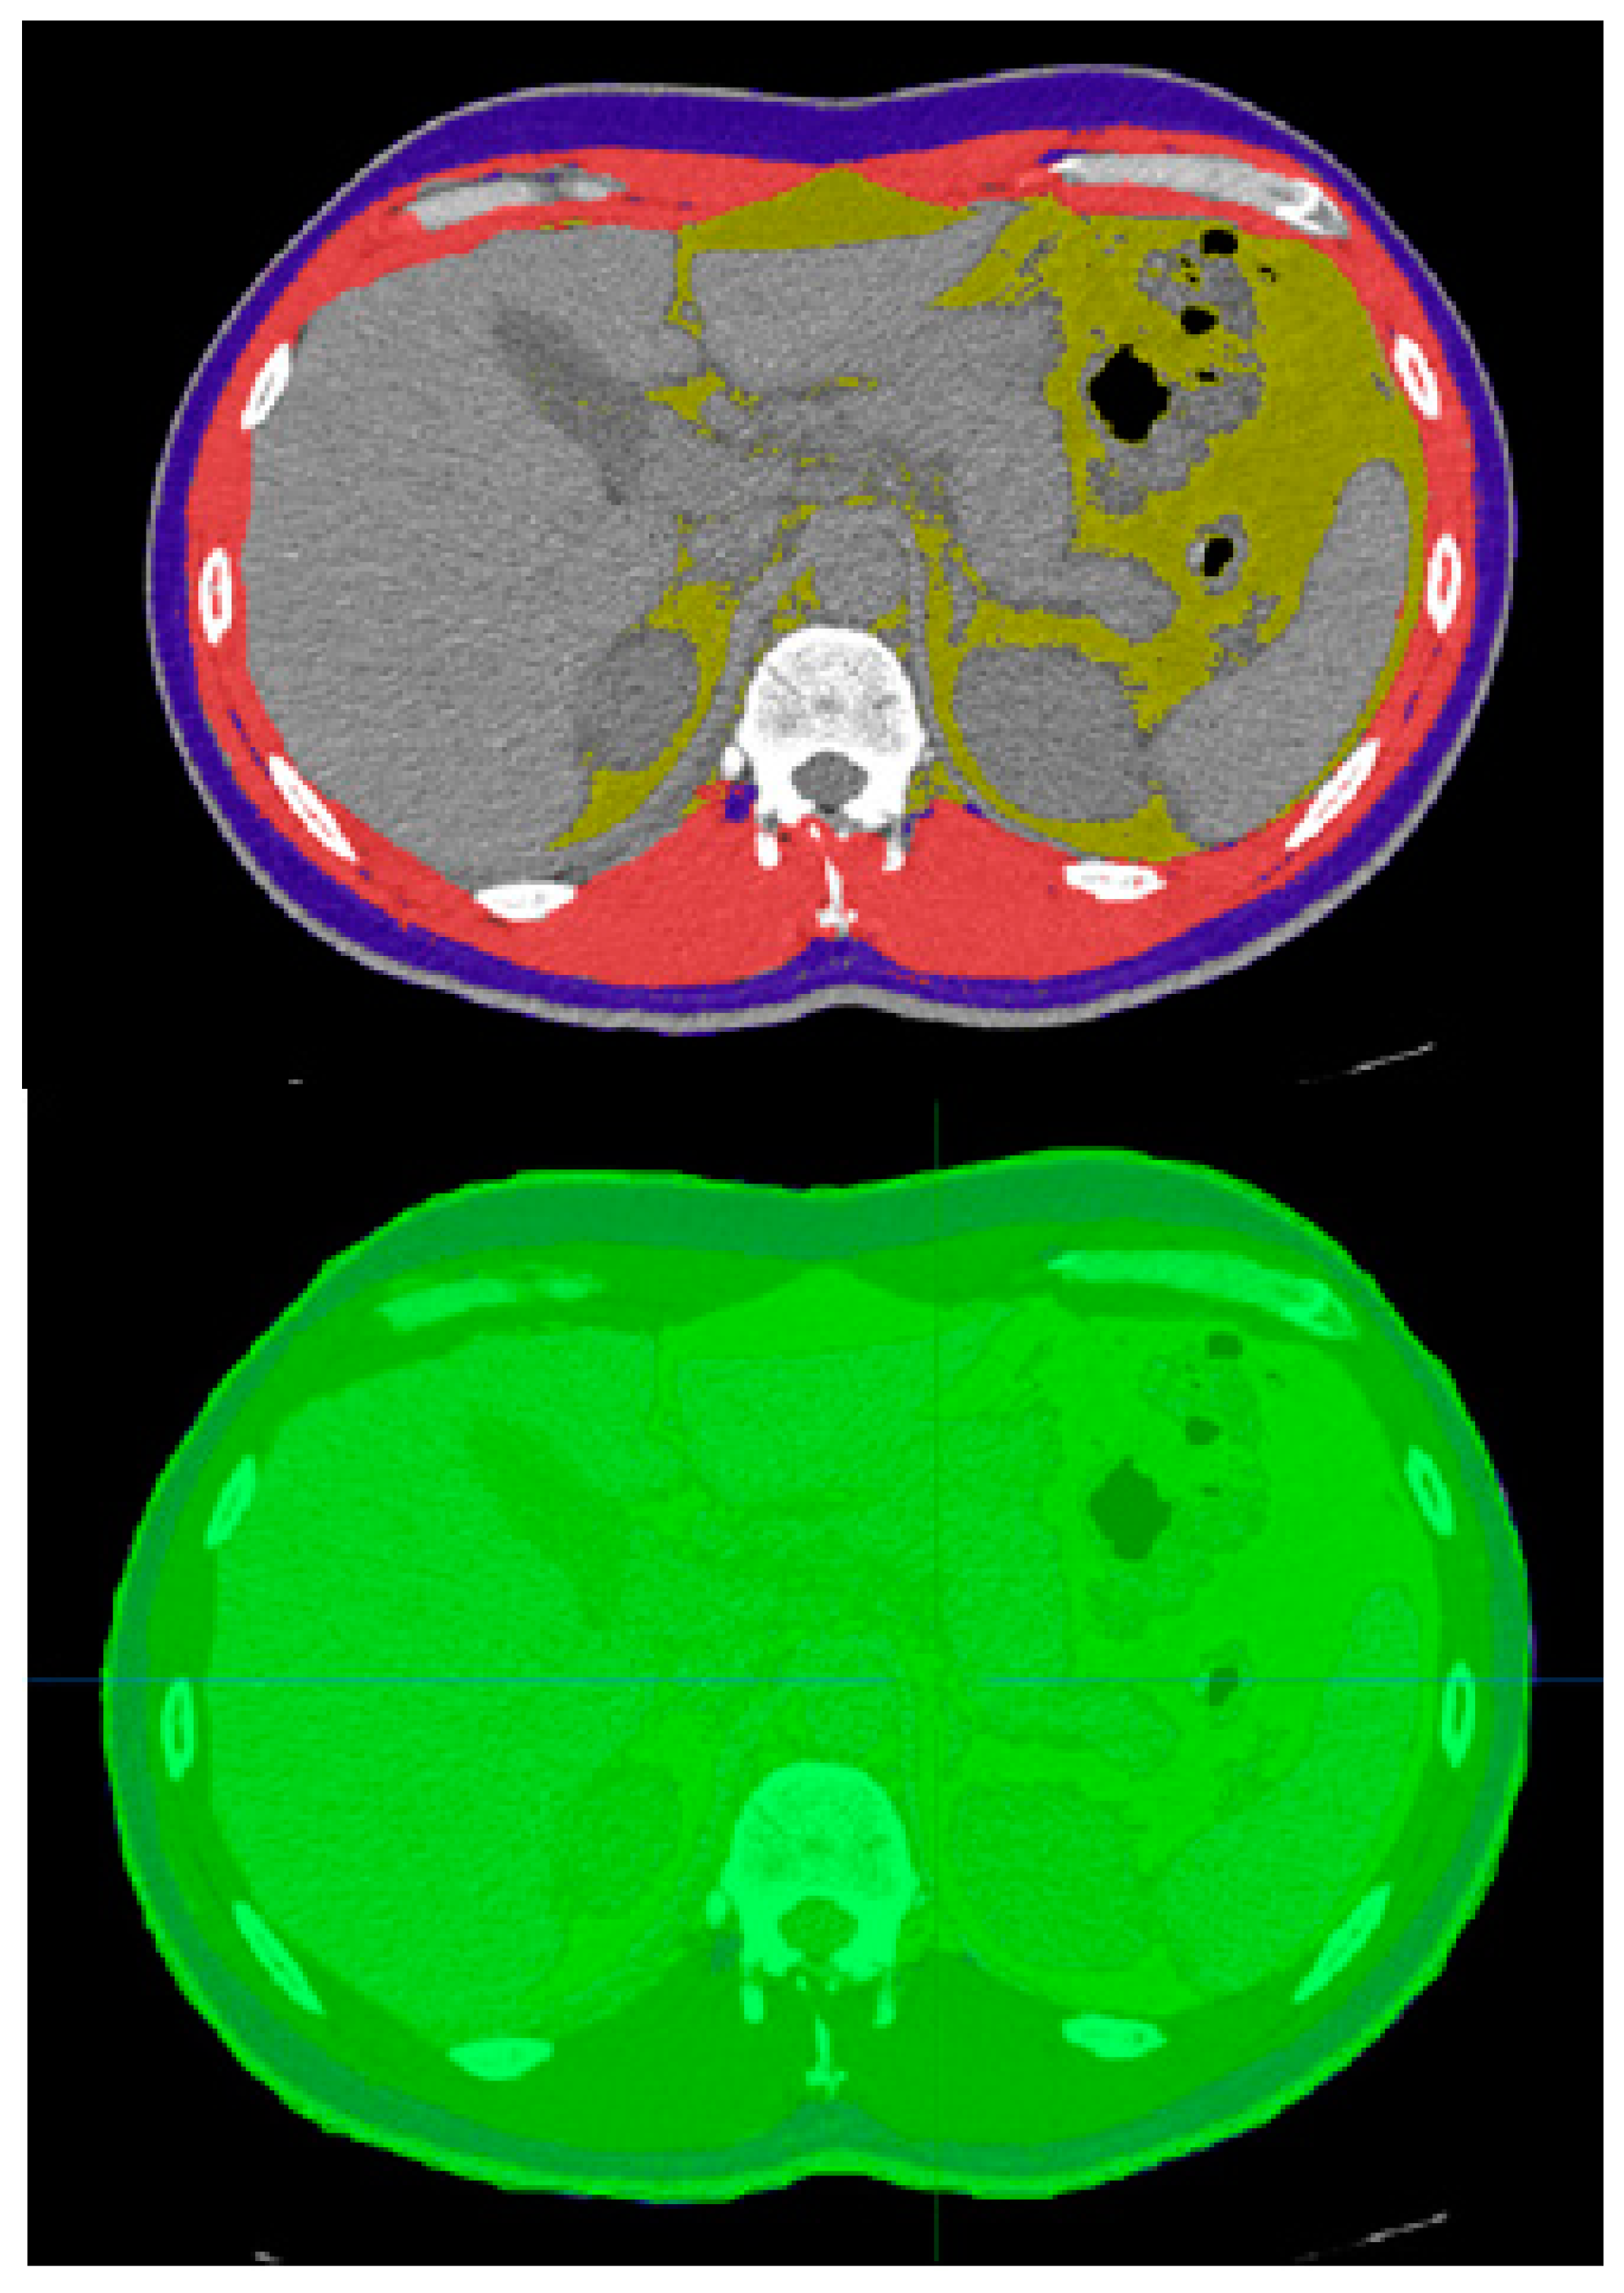

2.2. Data Analysis